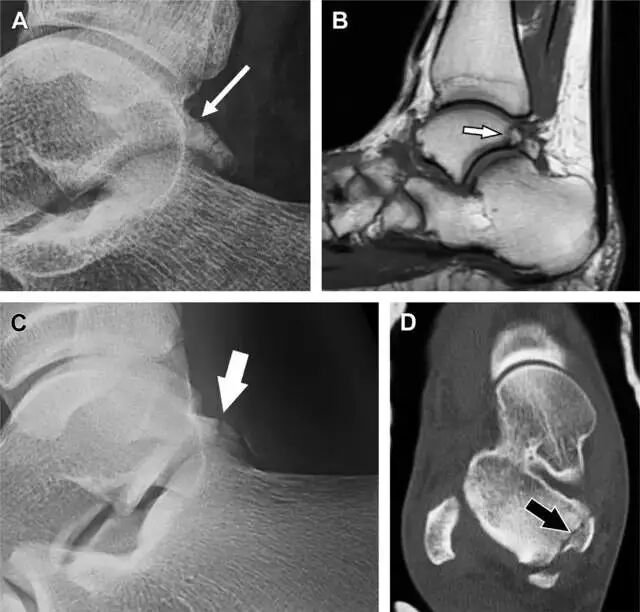

距骨后突骨折

距骨后突有内侧结节和外侧结节,距骨后突内侧结节撕脱性骨折常发生在背屈内旋的暴力作用下。严重跖屈时,胫骨后缘和跟骨挤压距骨后突外侧结节呈楔形,易发生粉碎性骨折。这些骨折细微且需与三角骨鉴别。侧位片观察距骨后突骨折最佳,常规拍片很难发现,当高度怀疑这种骨折又没法做 CT 时,建议加做多个角度的外旋斜位片(图 5)。

图 5 距骨后突骨折。侧位片(A)和 MRI 矢状位 T1 加权像(B)均示后外侧突的简单骨折(箭头),再次阅片时才发现 X 线片上的骨折;侧位片(C)和 CT 横断面图像示后内侧突的粉碎型骨折(箭头)

跟骨前突骨折

呈 Y 形的分歧韧带附着于跟骨前突上,是维持踝关节跖屈和背屈稳定性的重要结构。跟骨前突骨折常发生于足跖屈内旋、分歧韧带被牵拉时,或者足背屈外旋、骰骨和距骨挤压前突时。而这些骨折在初次 X 线检查时常常被漏诊掉。踝部侧位片诊断这些骨折最佳,准确诊断的关键点在于,必须仔细查看是否存在骨皮质中断(图 6)。如果侧位片可疑,建议加做斜位片协助诊断。

图 6 跟骨前突骨折。A 侧位片示跟骨前突骨折(箭头),与舟骨的重叠使骨折显示模糊;B 另一位患者的侧位片示内翻损伤所致的骨折(箭头),这种损伤机制引起小块的骨折